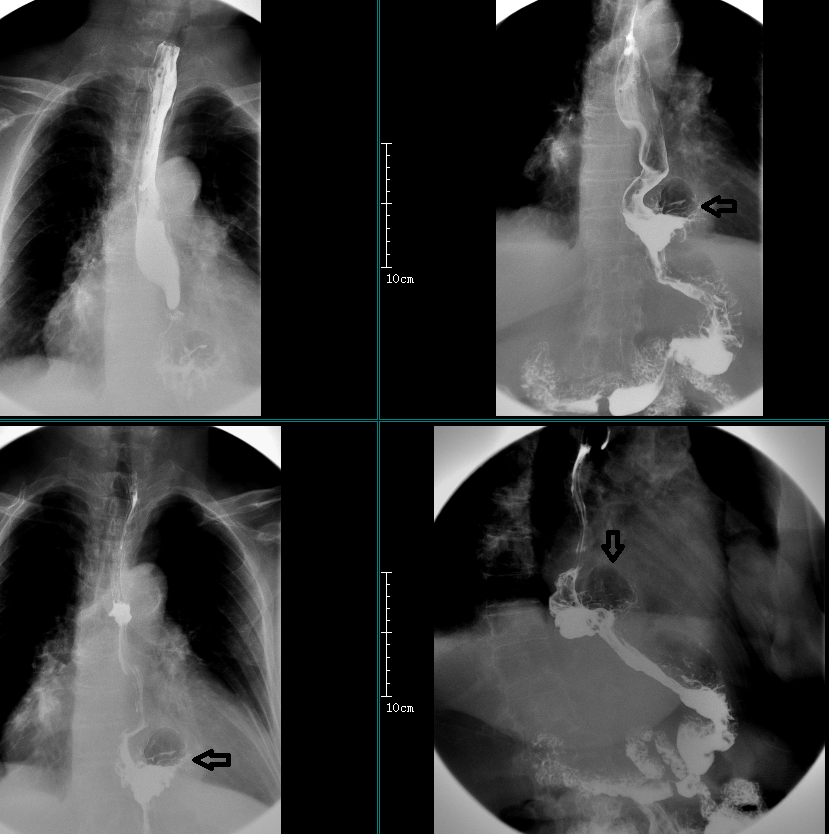

简要病史:女,83岁,反复胸骨后疼痛 3-4 天

食管全程扩张,管腔内大量食物及气体潴留,钡剂通过贲门受阻,呈鸟嘴状,钡剂间歇性流入胃腔,黏膜皱襞光整。

病例二

简要病史:女,58 岁,吞咽不适、腹胀。

食管中下段扩张,钡剂通过贲门明显受阻,呈鸟嘴状,黏膜皱襞光整。

进食哽噎 20 年,加重伴不能进食、呕吐 4 天:

食管扩张,管腔内大量食物潴留,钡剂通过明显受阻,呈鸟嘴状、漏斗状,钡剂缓慢通过。